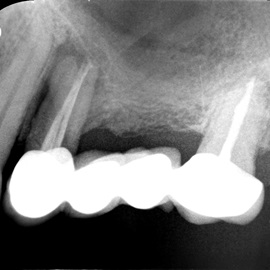

Pacjent z długą historią leczenia implantologicznego. Pierwsze implanty w pozycjach 23, 24 miał wkręcane w Warszawie przed 25 laty. Implant w pozycji górnego prawego kła ma agresywny gwint, ponieważ bezpośrednio po implantacji był obciążony (immediate loading) tymczasowym atachmentem ball abutmentv do stabilizacji tymczasowej protezy ruchomej. Kość szczęki regenerowana i odbudowywana etapami w całym górnym prawym kwadrancie. Pacjent planuje uzupełnić brakujące zęby 25, 26.

Odbudowa - lewy górny kwadrant 23,24,25. Po operacji lewej zatoki szczękowej metodą caldwell-Lucka początkowo oceniona jako niekwalifikująca się do leczenia implantologicznego. Później warunkowo zakwalifikowana do odbudowy kości i tkanek miękkich.